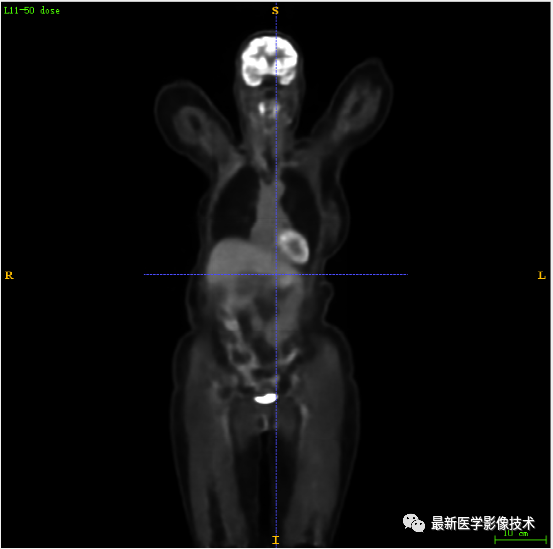

7.2、低剂量4重建结果

第一张是低剂量4的PET图像,第二张是full剂量PET图像,第三张是网络重建的PET图像。